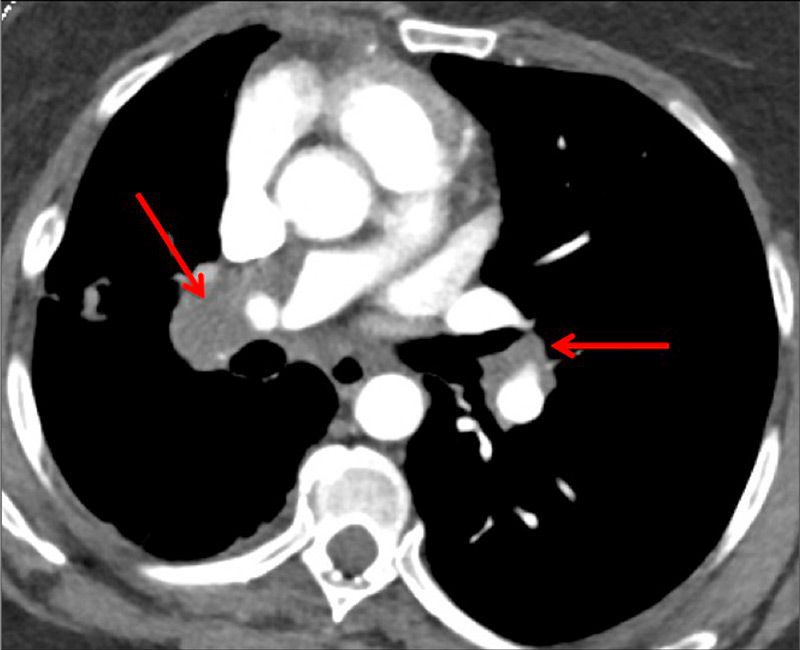

Figure 2

Chronic thromboembolic pulmonary hypertension (CTEPH). Vascular (A) and parenchymal (B) signs of CTEPH with proximal marginal occlusion (arrows) and mosaic pattern (stars). Functional information simply added with triangular perfusion defects (stars) on the iodine maps (C).